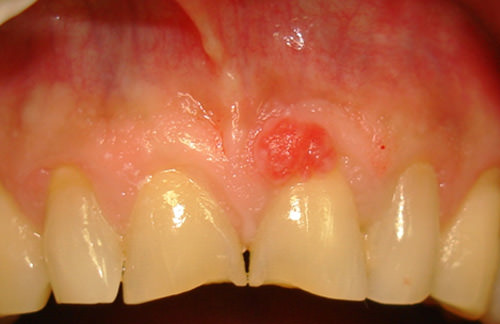

El paciente presenta al examen clínico una lesión en la encía marginal, por vestibular del 21, de forma ovoide (figura. 1), con 5 mm de diámetro (figura. 2), consistencia blanda, textura rugosa, base sésil, color rojizo, crecimiento lento e indoloro, y de 18 meses de evolución.

Fig. 1

Granuloma Piógeno

Fig. 2

Granuloma Piógeno. Lesión de 5mm aproximadamente